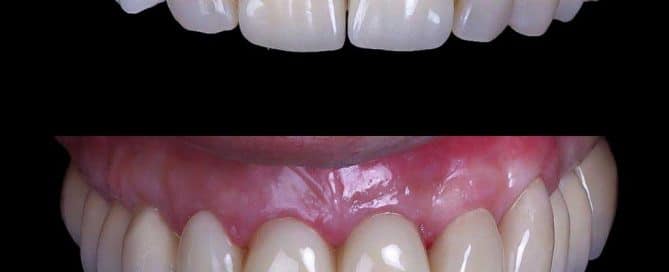

SITUACIÓN INICIAL Paciente que viene a Clínica MAG Dental por [...]